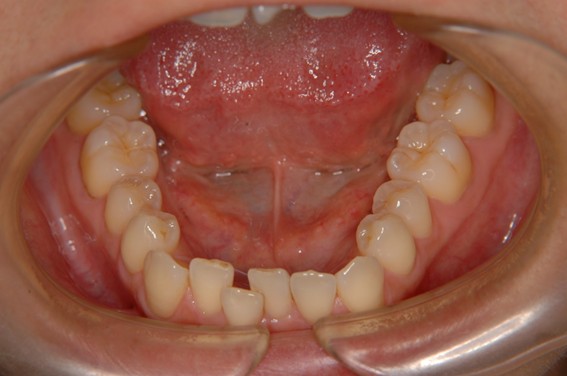

| 主訴 | 前歯が逆に噛んでいるところがある。歯のがたつき。 |

| 治療内容 | 表側ワイヤー矯正、4本抜歯を行いました。 |

| 治療費 | 880,000円+ダイレクトボンディング33,000円(税込) |

| 治療期間 | 30ヶ月 |

| 治療回数 | 30回 |

| 想定されたリスク | 歯根吸収、歯髄壊死、歯髄充血、歯肉退縮のリスクがありました。 |